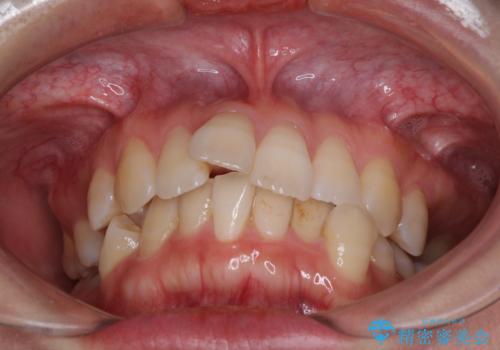

- 上下の歯の前後関係が乱れ、歯に負担がかかるとのことで来院された患者様です。

下顎が右左側に変位しているため、左側奥歯の咬み合わせが上下反対の関係となっていました。

また、上下ともに歯列が狭窄しており、奥歯以外にも反対咬合が認められました。